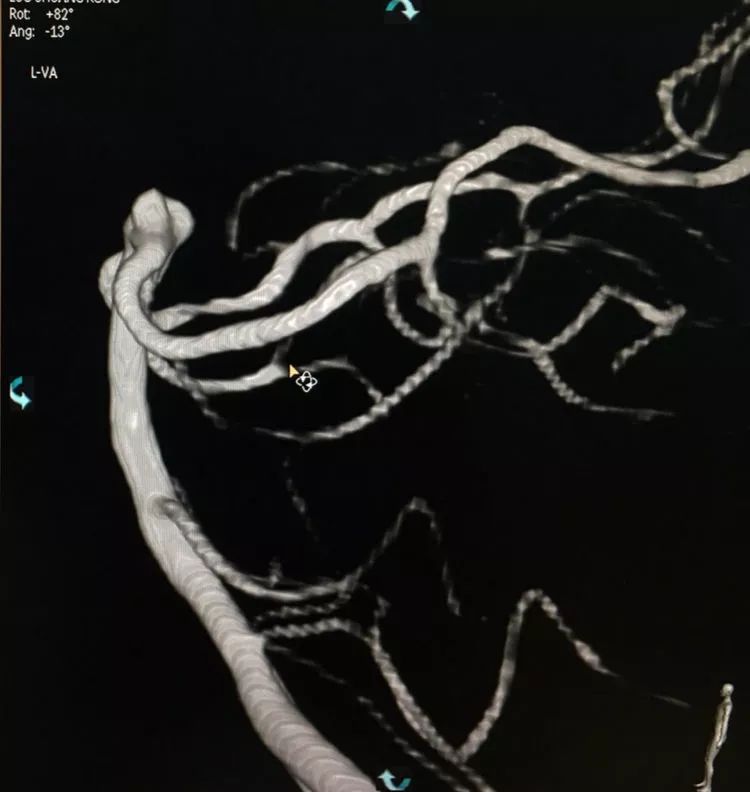

左椎动脉造影三维重建和测量

回头再观察左椎动脉造影的三维成像,发现瘤腔确实有向后方突出的分叶,明确弹簧圈团后部的空虚处仍是瘤腔的一部分

此刻微导管的管头被支架压在瘤腔前部,显然无法再深入到瘤腔后部的死腔,这根直头的微导管该结束使命了,

换用一根新的Echelon10微导管,头端塑成C型,以Arvigo14微导丝引导(先前的Sychro14微导丝的头端已经有损了),经LVIS支架内部接近瘤腔后部的死腔,但微导丝可以进入死腔,微导管头死活钻不进去,被LVIS支架的网丝挡住去路,怎么办?那就隔着渔网袜挠痒!

微导管头顶在支架网眼处,投送一枚1.5-2的小圈,一开始弹簧圈走行入载瘤动脉(支架)内,用扭具调整弹簧圈头端的行进方向,并随之微调微导管头的方向和张力,圈终于成功钻入死腔!

再投入一枚1.5-3的小圈

继续钻入一枚1.5-2的小圈

嗯,完美收官!

回到工作位造影,显示基底动脉顶端动脉瘤完全栓塞,基底动脉顶端四根血管畅通。

术后左椎动脉正位、侧位的造影和蒙片